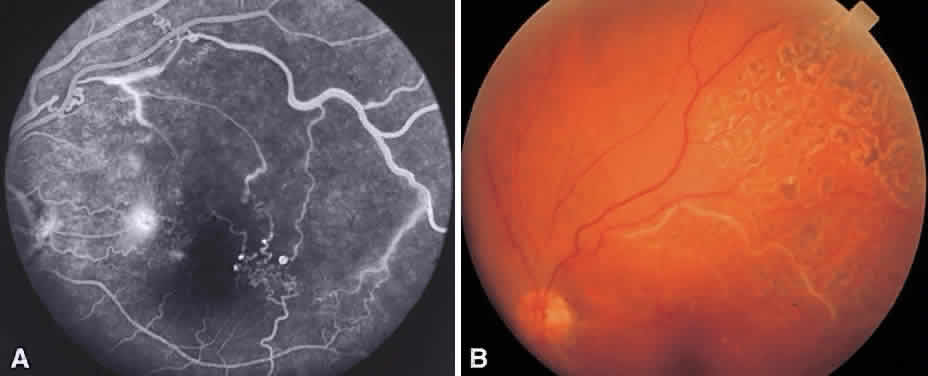

Occasionally PRP fails to induce regression of neovascularization and vision decreases. This can be a result of increased macular edema, focal bleeding from persistent neovascular fronds, retinal detachment, or neovascular glaucoma. Regression of HRCs occurs in 70% of cases within 3 weeks of treatment.33 Not surprisingly, patients who demonstrate a favorable early objective response to laser therapy have a significantly better visual prognosis than those who do not.34 In the case of increasing NVD or persistent NVD with bleeding, supplemen-tal treatment may be helpful. Peripheral retinal cryo-ablation may also be effective in causing regression of NVD or NVE. Cryotherapy is especially helpful in the setting of significant media opacities. About six applications are necessary in each quadrant. If vitreous hemorrhage has occurred and appears to be nonclearing, vitrectomy surgery may be indicated.